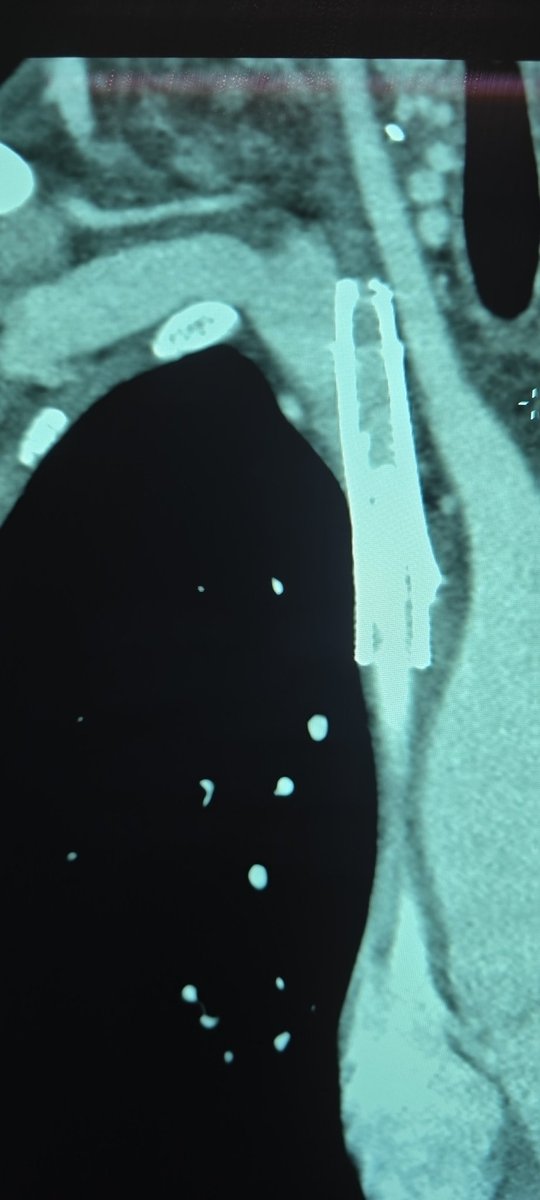

What better way to start holiday weekend call than a TIPS PR

Bleeding tips:

22 mins from lido to pressure, single stick w/ #ScorpionX

Gradient 27>8mmHg, 8cm Viatorr

#ICETIPS @WLGore @ArgonMedical

Props again to @tarheeldylan and @_backtable (episode 455 for basic technique)